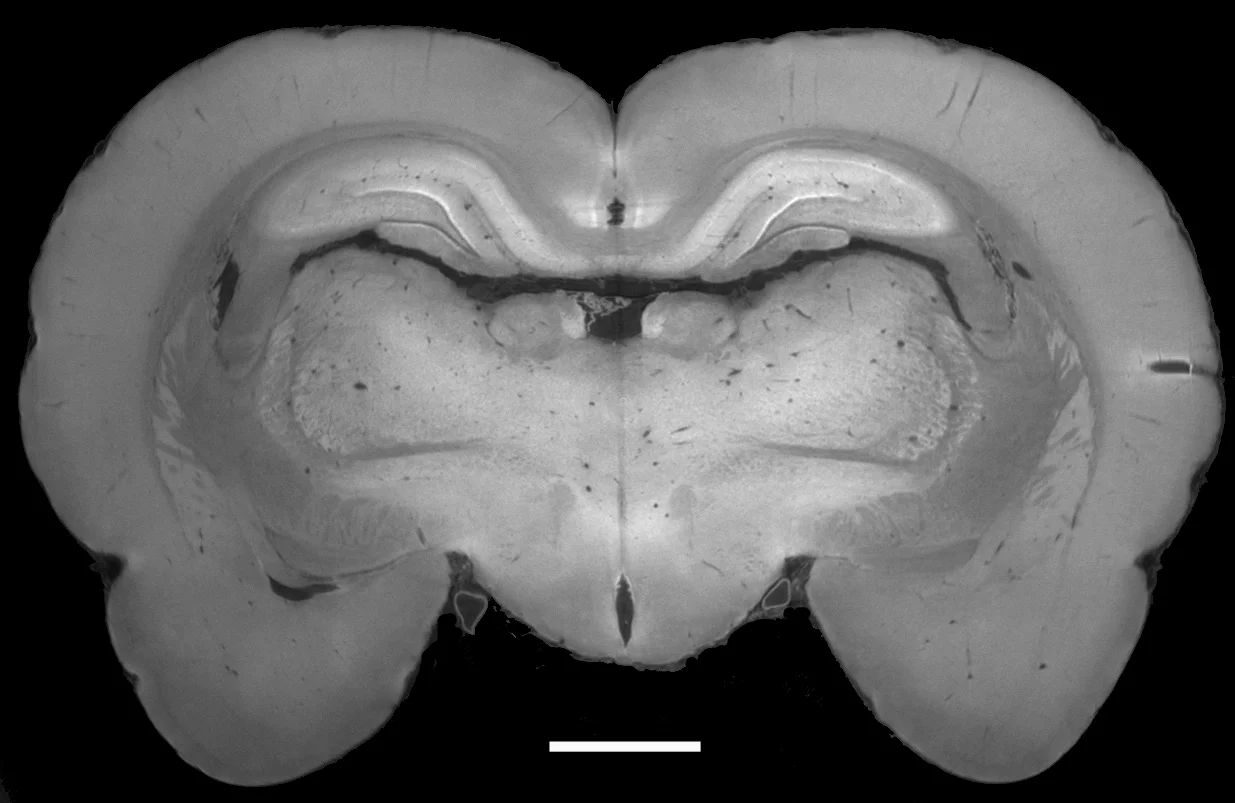

Klassische Röntgenbilder können Knochen gut von Weichgewebe unterscheiden – Muskeln, Knorpel, Sehnen oder Weichteiltumore sehen in den Bildern aber fast gleich aus. Mit dem Phasenkontrastverfahren, wie es vor wenigen Jahren am Paul Scherrer Institut entwickelt wurde, lassen sich Röntgenbilder erzeugen, in denen auch diese Gewebearten klar unterscheidbar sind. Nun haben Forschende des Paul Scherrer Instituts und der Chinesischen Akademie der Wissenschaften das Verfahren so weiterentwickelt, dass es in Zukunft so einfach zu handhaben sein wird wie gewöhnliche Röntgenaufnahmen. Die Forschenden erwarten, dass das Verfahren zukünftig helfen wird, in der Arztpraxis Tumore zu erkennen oder am Flughafen gefährliche Gegenstände im Gepäck sichtbar zu machen. Über ihre Ergebnisse berichten die Forschenden diese Woche in der Online-Ausgabe der Zeitschrift der Amerikanischen Akademie der Wissenschaften (PNAS – Proceedings of the National Academy of Sciences of the United States of America).

Um aus den Phasenunterschieden ein Bild der Gewebestruktur zu bekommen, schicken die Forschenden das Licht durch ein feines Gitter mit Abständen von einigen tausendstel Millimetern, sodass sich die verschiedenen Strahlen überlagern. Aus der Überlagerung bestimmen sie dann die Struktur in einer bisher unerreichten Genauigkeit. Das schweizerisch-chinesische Forscherteam hat nun das Verfahren „Reverse Projection Method – RP“ erarbeitet, mit dem man die Phasenverschiebungen auf eine sehr einfache Weise bestimmen kann.